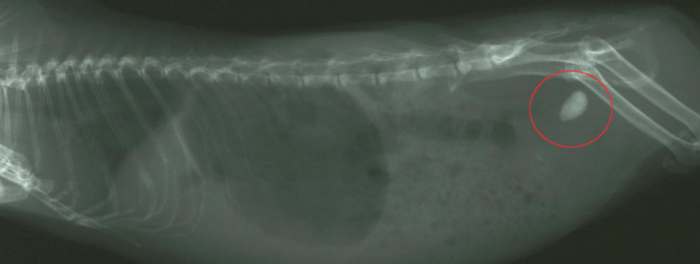

Abbildung: Blasenstein beim Meerschweinchen.

Blasenstein beim Meerschweinchen